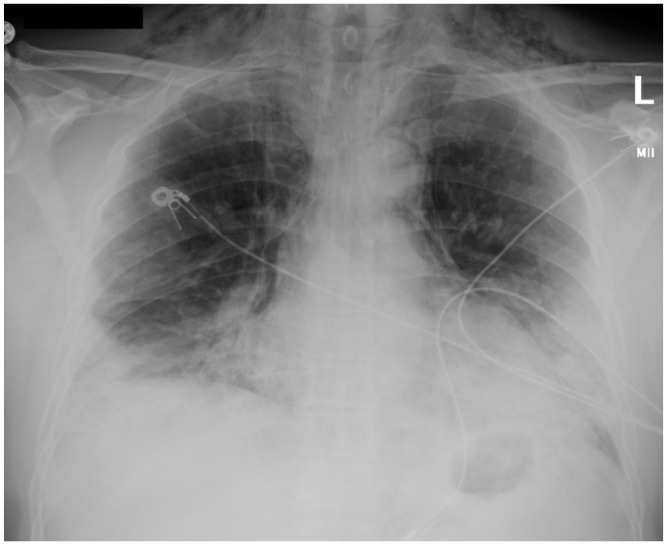

Blood test results showed elevated leukocytes at 17,200 (4500–10,000 cells/µL) with neutrophils 15,700 (1800–8000 cells/µL) and lymphocytes 900 (1200–3300 cells/µL), procalcitonin level of 0.27 (⩽0.09 ng/mL), and C-reactive protein concentration of 23.6 (0–0.74 mg/dL). Arterial blood gas at admission revealed metabolic alkalosis with arterial pH of 7.47, partial pressure of oxygen of 93 mm Hg, arterial bicarbonate of 29.8 (22–26 mmol/L), and normal partial pressure of carbon dioxide. Chest X-ray done at admission showed confluent bilateral ground-glass opacities and pneumomediastinum with subcutaneous emphysema at the base of the neck (Figure 1). No pleural effusion, pleural thickening, or pneumothorax was noted. Computed tomography (CT) thorax without contrast confirmed bilateral peripheral consolidation and revealed diffuse pneumomediastinum (Figures 2 and 3).

Figure 1.

Initial chest X-ray. This is a chest radiograph showing evidence of pneumomediastinum, subcutaneous emphysema tracking into the neck base soft tissues, and diffuse ground-glass and consolidative opacities bilaterally and peripherally.